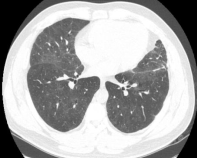

这位慢性纤维化型过敏性肺炎患者就可以看到三种密度征、磨玻璃影、网格影、牵拉性支气管扩张,没有蜂窝。

三种密度征(Three density pattern)里的三个区域分别是:高密度区提示磨玻璃影子,低密度区提示小气道疾病所累及的肺脏出现了气体陷闭的表现,还有一些正常的肺脏。

当出现三种密度征的时候,结合临床,能够高度提示这个患者是 HP。